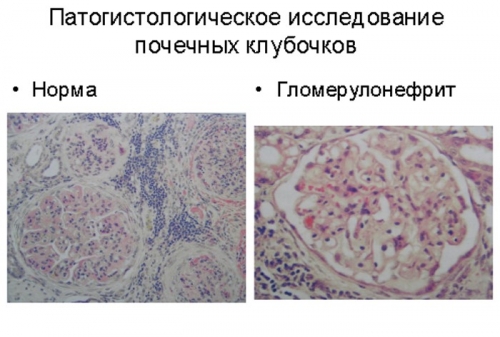

Симптомы подострого гломерулонефрита: фото и описание

Раздел: Визуальный дайджест